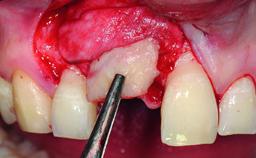

A 49-year-old female patient was referred for implant therapy to replace the upper right central incisor (tooth 11). The tooth had been assessed by an endodontist who diagnosed a vertical fracture of the root. The tooth had a hopeless prognosis and needed to be extracted. The patient was healthy and was not taking any medications. She was allergic to penicillin. The patient had high esthetic demands but her expectations were realistic. The extraoral examination revealed no facial asymmetries. The right temporomandibular joint demonstrated an opening click but was otherwise asymptomatic. The lip line was high with a significant gingival display.

Bone Augmentation Simultaneous|Vertical

Augmentation Materials Autogenous chips|Xenogenous|Membrane

Bone Volume Deficient vertically or deficient vertically AND horizontally